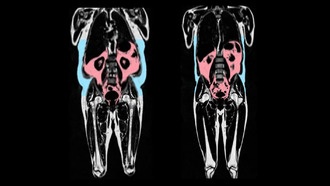

10 минут интенсивных упражнений могут замедлить рост раковых клеток Новое исследование учёных из Университета Ньюкасла показало, что даже короткая 10-минутная интенсивная тренировка может оказывать мощное противораковое действие, в частности, против колоректального рака.Исследование, опубликованное в International Journal of Cancer, выявило, что кратковременная